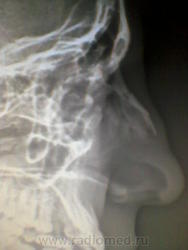

Здравствуйте уважаемые коллеги , я написала в заключении перелом костей носа без смещения , посмотрите пожалуйста есть ли смещение?

Если и есть, то незначительные.

Полностью судить о смещении можно на снимках в 2-проекциях. Здесь это невозможно. Написал бы просто "Перелом костей носа" не указывая, что "без смещения". А вот если БЫ смещение было БЫ, то указал БЫ и его.

То, что для крупной трубчастой кости - незначительное смещение, для костей носа может оказаться серьезным косметическим дефектом. но как бы мы не "мудровали" по рентгенограммам, на КТ это самое смещение выглядит совсем по другому))))

Смещение есть. По снимкам костей носа оценивается смещение только в 1 плоскости, а фронтальное может быть значительным.

Всегда пишите "без смещения в сагиттальной плоскости". Это я понял после того, как ЛОР мне поругался: там же нос набок.

Я прямую проекцию тоже сделала но если честно здесь ничего информативного не увидела . Спасибо за советы .

Я прямую проекцию тоже сделала .

Бокового снимка нет. Но иногда очань ценную информацию дает аксиальная проекция.

Интересно, а по снимку в боковой проекции, имеют место быть одна, или две линии перелома?

Уважаемый Валентин Львович здравствуйте , да я отметила две линии перелома ,насчёт смещения ничего не написала потом ЛОР врач спросил я ответила что не вижу смещения. Хочу отметить что это первый случай( перелом костей носа) в моей очень маленькой практике. Спасибо всем за советы!

Ну, вот и отлично! Первый случай в Вашей практике, и Вы оказались на высоте - заметили и описали.

Еще совет вдогонку: "не вижу" - это слишком личное, подразумевает, что кто-то другой увидит, а Вы нет Лучше говорить (даже говорить) "не определяется". Удачи!